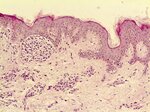

Гистопатологическое заключение:

сложный пигментный невус с тяжелой дисплазией 3 степени.

Фото гистологических срезов:

Borozdka40_1.jpg